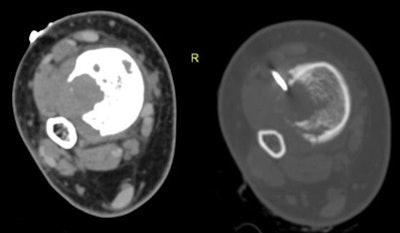

In all, 49 patients including 23 men and 15 women (mean age 33.7 years, range 4-77 years) underwent image-guided biopsies. Imaging in the cohort included radiography, CT, and MRI, and the study team categorized the records according to the location of the host bone, presence or absence of an extraosseous soft-tissue component (usually at MRI), and imaging nature of the lesion matrix (usually at CT) including lytic, sclerotic, or mixed lytic and sclerotic.

After bleeding, the researchers collected procedure parameters and lab markers. An experienced musculoskeletal radiologist performed all biopsies under CT guidance, with most patients in a state of conscious sedation so they could lie down comfortably, the authors wrote.

Cross-sectional imaging showed an extraosseous component in about half (26/49) patients, which facilitated biopsy and obviated the need for cortical breach, the authors wrote. The other 23 patients had completely intraosseous lesions that required more aggressive efforts to reach the lesion, the study team wrote.

Based on imaging findings at CT and x-ray, initial diagnostic yield was higher for mixed lesions (94%), followed by sclerotic (89%) and lytic (83%) lesions, according to the authors. As for the completely intraosseous lesions, the diagnostic yield was 74%, while the presence of extraosseous soft-tissue components raised the diagnostic yield to 100% in 26 cases.

"The image-guided percutaneous biopsy has proved to be a safe, minimally invasive, and cost-effective procedure for the diagnosis of skeletal lesions, obviating the need for the more risky and invasive open surgical biopsy in most patients, wrote Nouh and Abu Shady. "Meticulous technique regarding compartmental barriers, neurovascular structures, and seeding of malignant cells along the biopsy needle track are prerequisites for optimized treatment strategies with limb-salvage procedures. CT has proven to be a recognized modality for guiding PCNB of deep-seated musculoskeletal lesions."